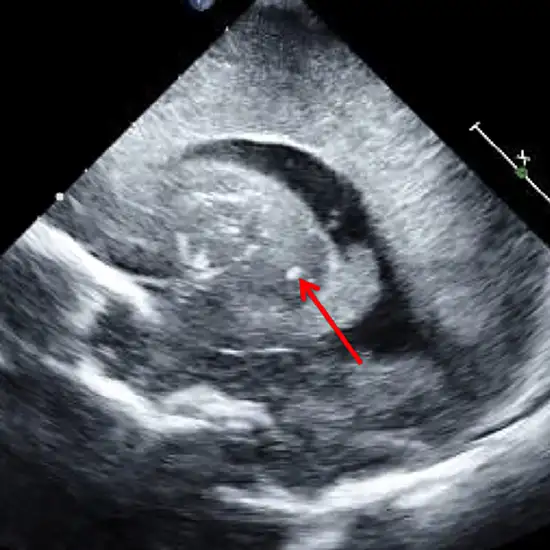

Cranial ultrasound is the imaging of the head that creates images of the brain and cerebrospinal fluid. It is most often performed on infants whose skulls have not yet developed entirely.

Babies are most often given this test. It looks for problems caused by being born too soon. It can be used on babies up to about 18 months old to check for problems in the brain and ventricles.

It helps diagnose problems such as periventricular leukomalacia (PVL causes damage to the brain tissue surrounding the ventricles.) and intraventricular haemorrhage (IVH is bleeding in the brain).

Cranial ultrasonography can help assess a baby's growing head size. The test can also check for brain infection (encephalitis or meningitis).